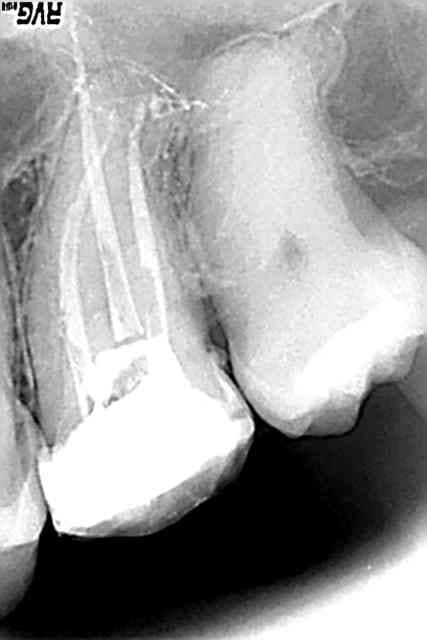

joli joli, surtout pour les canaux latéraux.

Le seul truc qui me chiffonne un petit peu, c'est le manque de densité de l'obtu sur certaines portions du canal, comme au milieu de ta racine MV. On y voit encore la trace du plugger du systéme B. difficulté pour remplir la moitié coronaire du canal? why? la gutta en cartouche du sybron n'est pas bien?

rien à voir tonio. il va y avoir un IC, alors à quoi ça sert d'obturer jusqu'en haut pour désobturer quelques minutes après...